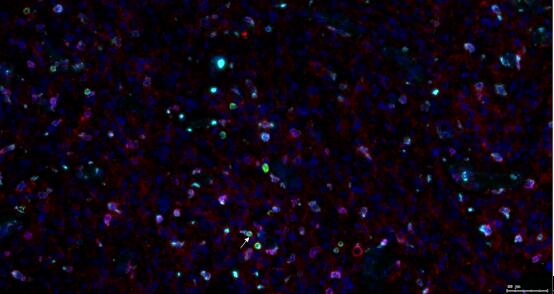

识别特殊细胞及其功能状态——通过共定位标示性 Marker 蛋白

双定位(两个蛋白):

三共定位(三个蛋白):

四共定位: